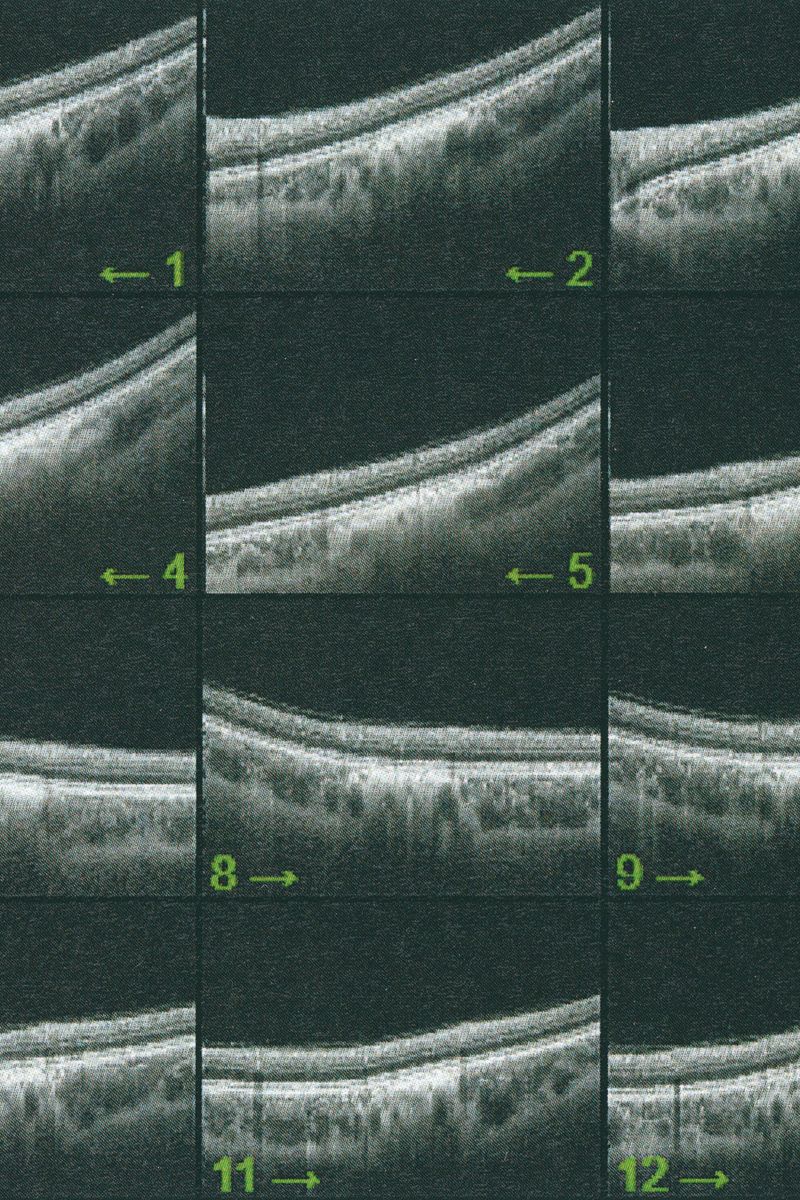

Following a terrifying experience with a too high dose of LSD when I was 16, something has changed in the way I observe visible reality. A hypertrophic screen materialized between me and the world, a scar of opacity. The fear of hallucination teaches a new language, so that every meaning remains trapped in a net and only the signifier filters through its meshes. No shadow, only empty light. Anguish arrests every retinal projection on that screen. Every perception is immobilized to be inspected for a hallucinatory return, it is reified, detached from its real referent, reduced to representation, incapable of referring to something outside of it. And behind (or in front) of it, the eyes have stolen consistency from reality. The body only appears occasionally, at the edges of the mind, when we engage in apperception. And yet I feel the tinkling of a gear that draws my attention inside my eye. I reflect on myself, I look back and from the inside. Once vision is situated in the empirical immediacy of the body, it belongs to time, to flow, to the end.

Collirio (Eye wash) is the attempt to demonstrate the non-absoluteness of visual experience, its nature as a situated, and yet, ambiguous act. It is the path that has allowed me to understand how my fears do not have roots in an unknowable place. The eye is not an unfathomable globe.